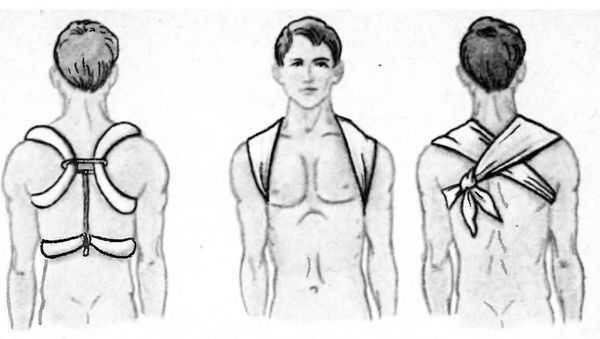

Есть много способов транспортной иммобилизации при переломе ключицы. Из имеющихся средств (бинтов, рубашек, полотенец) образуют 2 отдельных кольца. Лучше (если позволяет время) их делать из плотных ватно-марлевых жгутов. Кольца надеваются на руки, они должны проходить через подмышки, на спине завязываться между собой.

При стягивании колец между собой пострадавший говорит, на каком уровне он чувствует боль меньше всего, тогда окончательно закрепляют кольца. Под узел подкладывают мягкую ткань. Такую фиксирующую повязку называют кольца Дельбе, накладывать их можно на голое тело.

Важно! Недостаток этого способа заключается в том, что надплечия не поднимаются, значит, осколки повреждённой кости имеют возможность двигаться. Необходимы ещё другие методы фиксации.

Ещё один способ придания неподвижности повреждённой руке — 8-образная повязка. Она названа так по характерным движениям, которые проводятся вокруг тела пострадавшего человека. Такая повязка помогает поддерживать надплечия в разведённом положении.

Сначала бинт оборачивают вокруг грудной клетки несколько раз. Проходя по спине на лопатках и в подмышечных впадинах, фиксируются плотные подушечки. Затем переходят к 8-образной повязке. Перекрещивание бинта восьмёркой происходит на спине. Далее бинт уходит в подмышечную впадину, по грудной клетке пересечений нет. Бинтование проводится плотно, плечи должны приводиться в разведенное состояние. Такое положение облегчает потерпевшему болезненное ощущение.